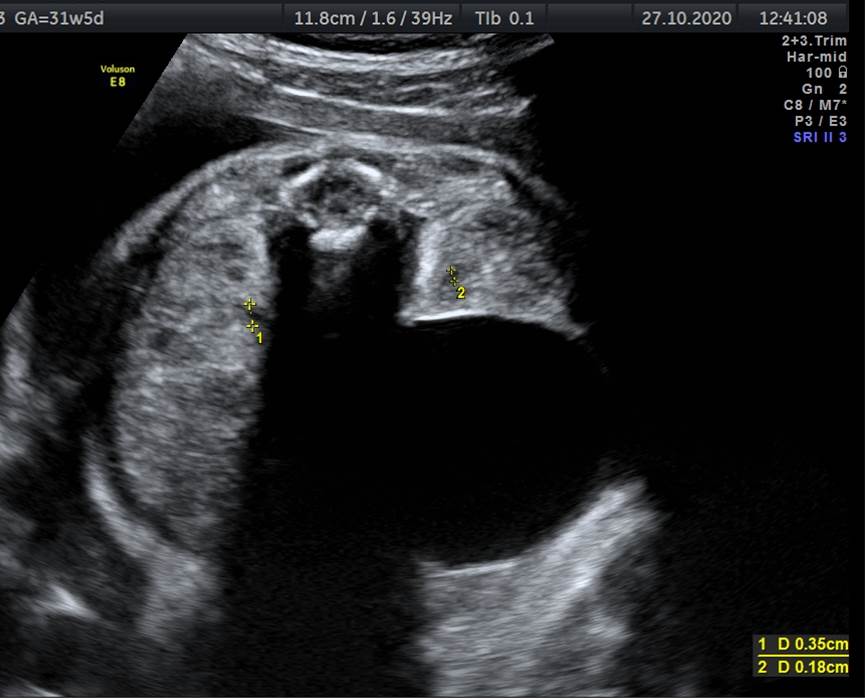

Вопрос 10

Оцените картину и укажите наиболее вероятный диагноз у плода женского пола в 31 неделю

- А — нормальный мочевой пузырь;

- Б – кишечная непроходимость;

- В – киста яичника;

- Г — киста селезенки

Комментарий к ответу 10

- Мочевой пузырь должен располагаться центрально, а здесь образование смещено латерально

- Для кишечной непроходимости характерно наличие нескольких анэхогенных образований, а здесь одно

- Для кисты селезенки характерно расположение в верхней трети брюшной полости и латеральнее желудка, а здесь образование располагается кпереди и ниже почки. Данная локализация, срок беременности и пол плода соответствуют кисте яичника